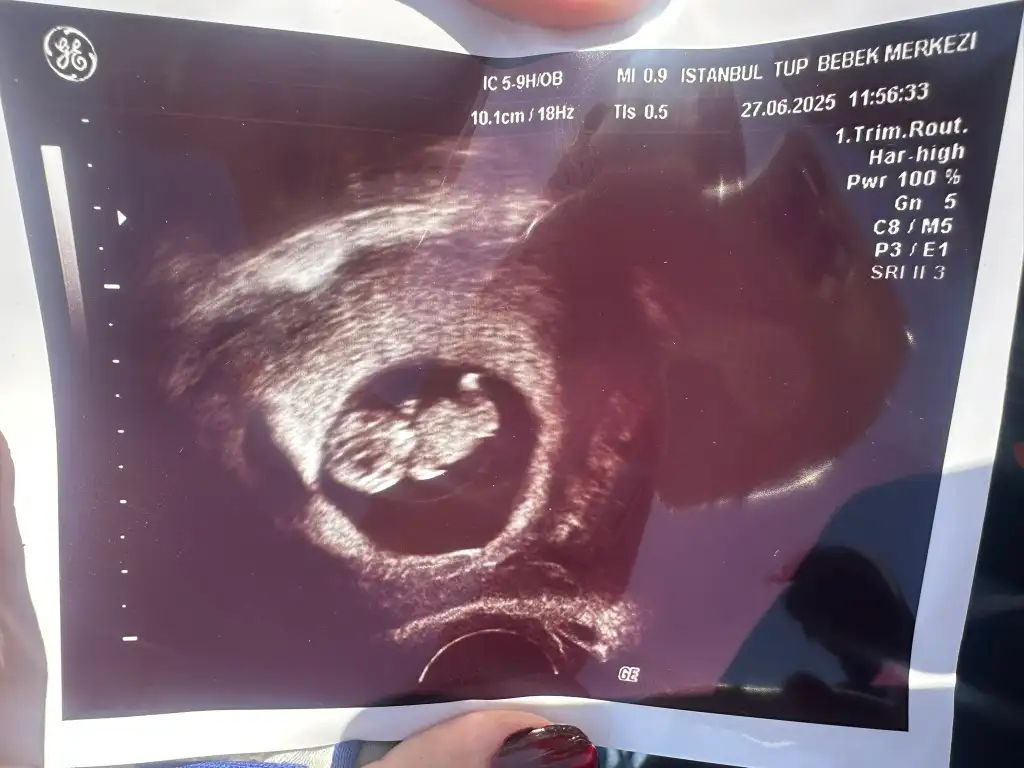

Bana da bakar mısınız lütfen biri 9 haftalık biri 6 haftalık karından ultrasonKese şekline göre erkek bence. Sağlıkla kucağınıza alın

Banada bakar mısnız lütfennnn çok merak ediyorum biri 9 haftalık biri 6 haftalık ultrason karından

Erkek bence. Sağlıkla kucağınıza alınBana da bakar mısınız lütfen biri 9 haftalık biri 6 haftalık karından ultraso

Sizin de karından ultrason mıBanada tahmin yapar msnzzz

EvetttSizin de karından ultrason mı

Tahmin edebilirmisiniz rica etsemErkek bence. Sağlıkla kucağınıza alın

Sanırım erkek sizinkiTahmin edebilirmisiniz rica etsem